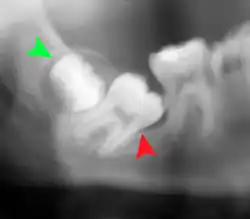

Impacted wisdom tooth with a backward tilt (distoangular impaction) and chronic infection to back of crown (green arrow)

Pericoronitis (green arrow) in lower right wisdom tooth

Impacted wisdom teeth without communication to the mouth, that have no pathology associated with the tooth, and have not caused tooth resorption on the blocking tooth, rarely have symptoms.[11] The chances of developing pathology on an impacted wisdom tooth that is not communicating with the mouth is approximately 12%.[11] However, when impacted wisdom teeth communicate with the mouth, food and bacteria penetrate to the space around the tooth and cause symptoms such as localized pain, swelling and bleeding of the tissue overlying the tooth. The tissue overlying the tooth is called the operculum, and the disorder is called pericoronitis which means inflammation around the crown of the tooth.[5]: 141  Low grade chronic periodontitis commonly occurs on either the wisdom tooth or the second molar, causing less obvious symptoms such as bad breath and bleeding from the gums. The teeth can also remain asymptomatic (pain free), even with disease.[7]